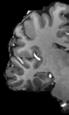

Finger tapping task: activation of Functional MRI a) Diffusion MRI and fiber tracking Post-mortem a) a) b) Fig 7 In a), an structural MPRAGE image acquired at 0 75mm isotropic (skull removed using FSL package) In b), fiber tracking based on DTI acquisition, 64 directions, 1 5mm isotropic resolution The colors are defined for different orientations of the fibers Fig 8: In a), susceptibility weighted images acquired at 0 35mm isotropic, 32 min acquisition time, in a post-mortem brain fixated with formalin In b), a photograph of similar slice in the same brain Table 1: 7T MRI studies conducted at the RF Research Facility at University of Pittsburgh White matter legions (circle): Multiple Sclerosis study Stroke (circle): sickle cell disease study Automatic hippocampus segmentation: Midlife Neurocognitive Lacunar infarct (arrow): depression study White matter hyperintensities (arrows): Healthy Brain aging study (left) and Small Vessels disease in preclinical Alzheimer’s disease study (right) Fig 9: Sample of some studies listed in Table 1 using the developed 16 array (Fig a) There are 4 completed studies and 13 ongoing patient studies with approximated 2 000 patients scheduled FUTURE DIRECTIONS 64-channel Tic-Tac-Toe RF transmit coil for 7T MRI 0 Fig 10: In a), the 64-channel transmit coil computational modeling [2] To improve the field of view of the projector/monitor in fMRI studies, the frontal panels can be removed, resulting in a 56-channel coil In b), one assembled side of the coil In c), simulated B1+ field distribution: for an 8kW power amplifier capabilities (default in older 7T MRI scanners) a homogeneity (measured by the coefficient of variationCV) of 15 2% is achieved in the brain For an 16 kW power amplifier (available for the recently FDA approved Siemens 7T MAGNETOM Terra), an CV of 10 6% can be achieved in the brain 16 kW power amplifier: 8 kW power amplifier: a) b) c) max